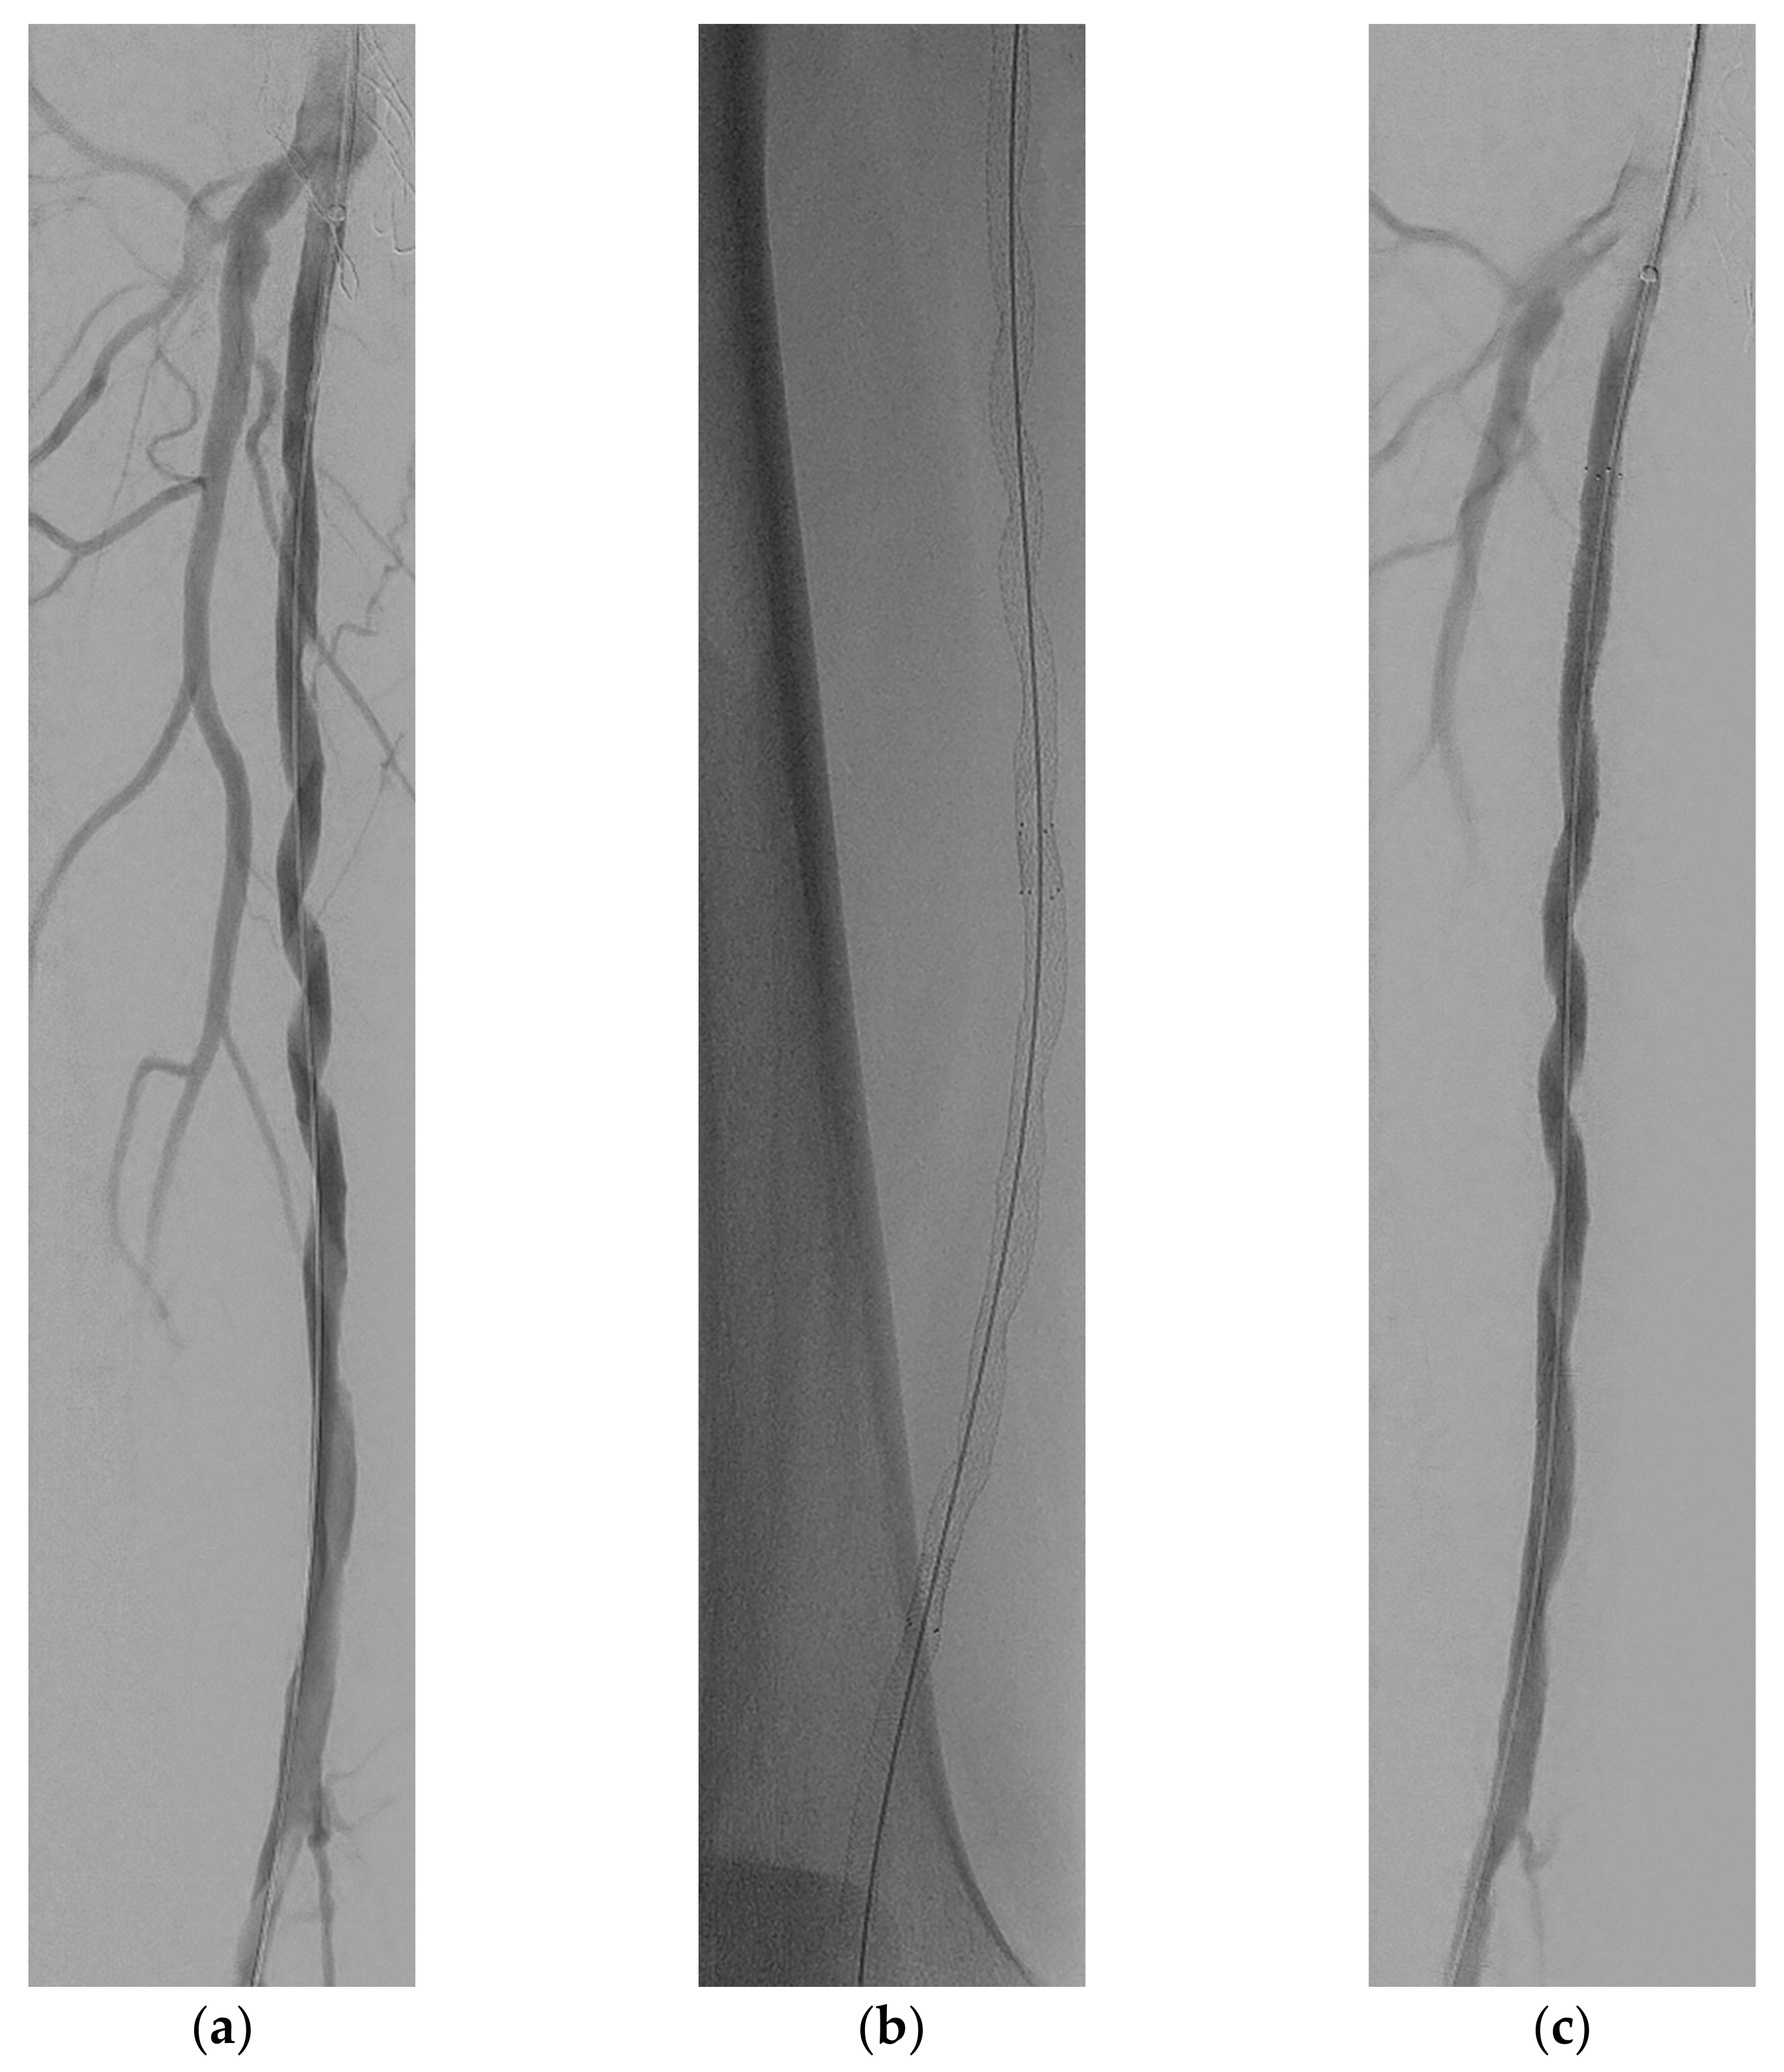

2. Case Report